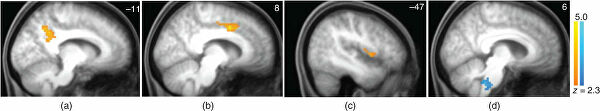

Желтый — утолщение левого предклинья, красный — левой верхней теменной доли у участников тренинга по медитации. Эти участки входят с нейронную сеть пассивного режима работы мозга

Одно из последних открытий — сеть пассивного режима (default mode network). Это крупная нейронная структура, связывающая разные участки мозга. Активизируется, когда человек уходит в себя, отключается от внешнего мира. В принципе, люди полжизни проводят в таком состоянии. Но к нему ведет и осознанная медитация.Чтобы глубже изучить пассивный режим мозга, ученые из Германии и Испании пригласили новичков пройти 40-дневный интенсивный тренинг по медитации. До и после эксперимента мозг сканировали, чтобы картировать активные участки по приливу к ним крови, насыщенной кислородом. Это БОЛД функциональная МРТ с регистрацией амплитуды низкочастотных флуктуаций, позволяющая исследовать мозг во время отдыха.Ученые доказали, что йога и медитация улучшают работу мозгаПосле тренинга у всех добровольцев обнаружили утолщение левого предклинья. Этот участок находится в теменной области коры и задействован в нейросети пассивного режима. В то же время амплитуда низкочастотных флуктуаций там снизилась, а сами люди отметили ослабление симптомов депрессии и стресса.